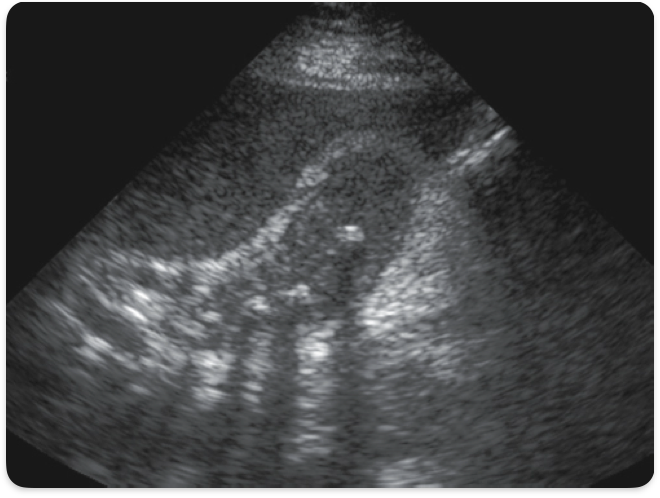

Rokitansky Aschoff sinuses

Pockets in gallbladder wall containing cholesterol crystals, causing comet-tail artifact. (Adenomyomatosis)

Adenomyomatosis